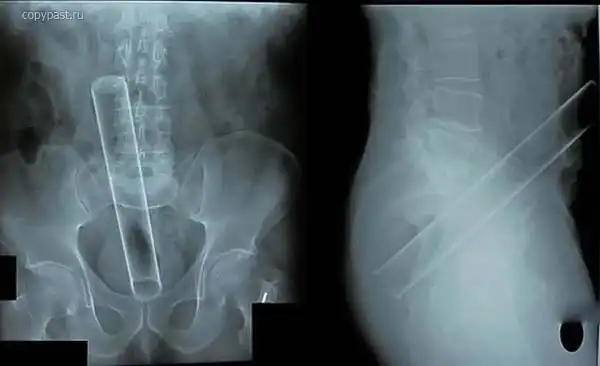

Огромный вибратор в заднице. Залез полностью. Без хирургического вмешательства

достать не смогли. Больные люди...